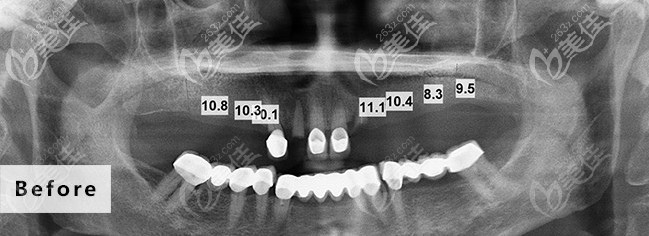

術(shù)前照片:

不檢查不知道,自己由于牙齒缺失多年,牙槽骨或多或少都有些萎縮了,不能做即刻負(fù)重種植,要做傳統(tǒng)的點(diǎn)種,我也不懂,就聽醫(yī)生的推薦,選擇了性價比比較高的德國種植體。

種植過程好像也蠻快的,我就記得我進(jìn)去后打了個麻藥,醫(yī)生拿個小鉆頭一樣的東西在嘴里一直動,沒多久就好了,也不疼不癢的,據(jù)醫(yī)生說我這個一共植入了7顆植體,還給我看了植體植入后的圖片,我也看不懂,植入植體后戴上臨時牙冠,似乎跟真牙一模一樣,三個月后等待植體穩(wěn)定后就可以更換牙冠后就能吃飯用了。